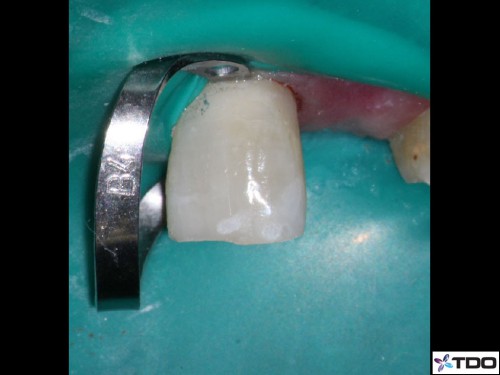

47 yof. Symptomatic partially necrotic pulp. First visit instrumented with #15K to length. Second visit apically gauged to a size 40.